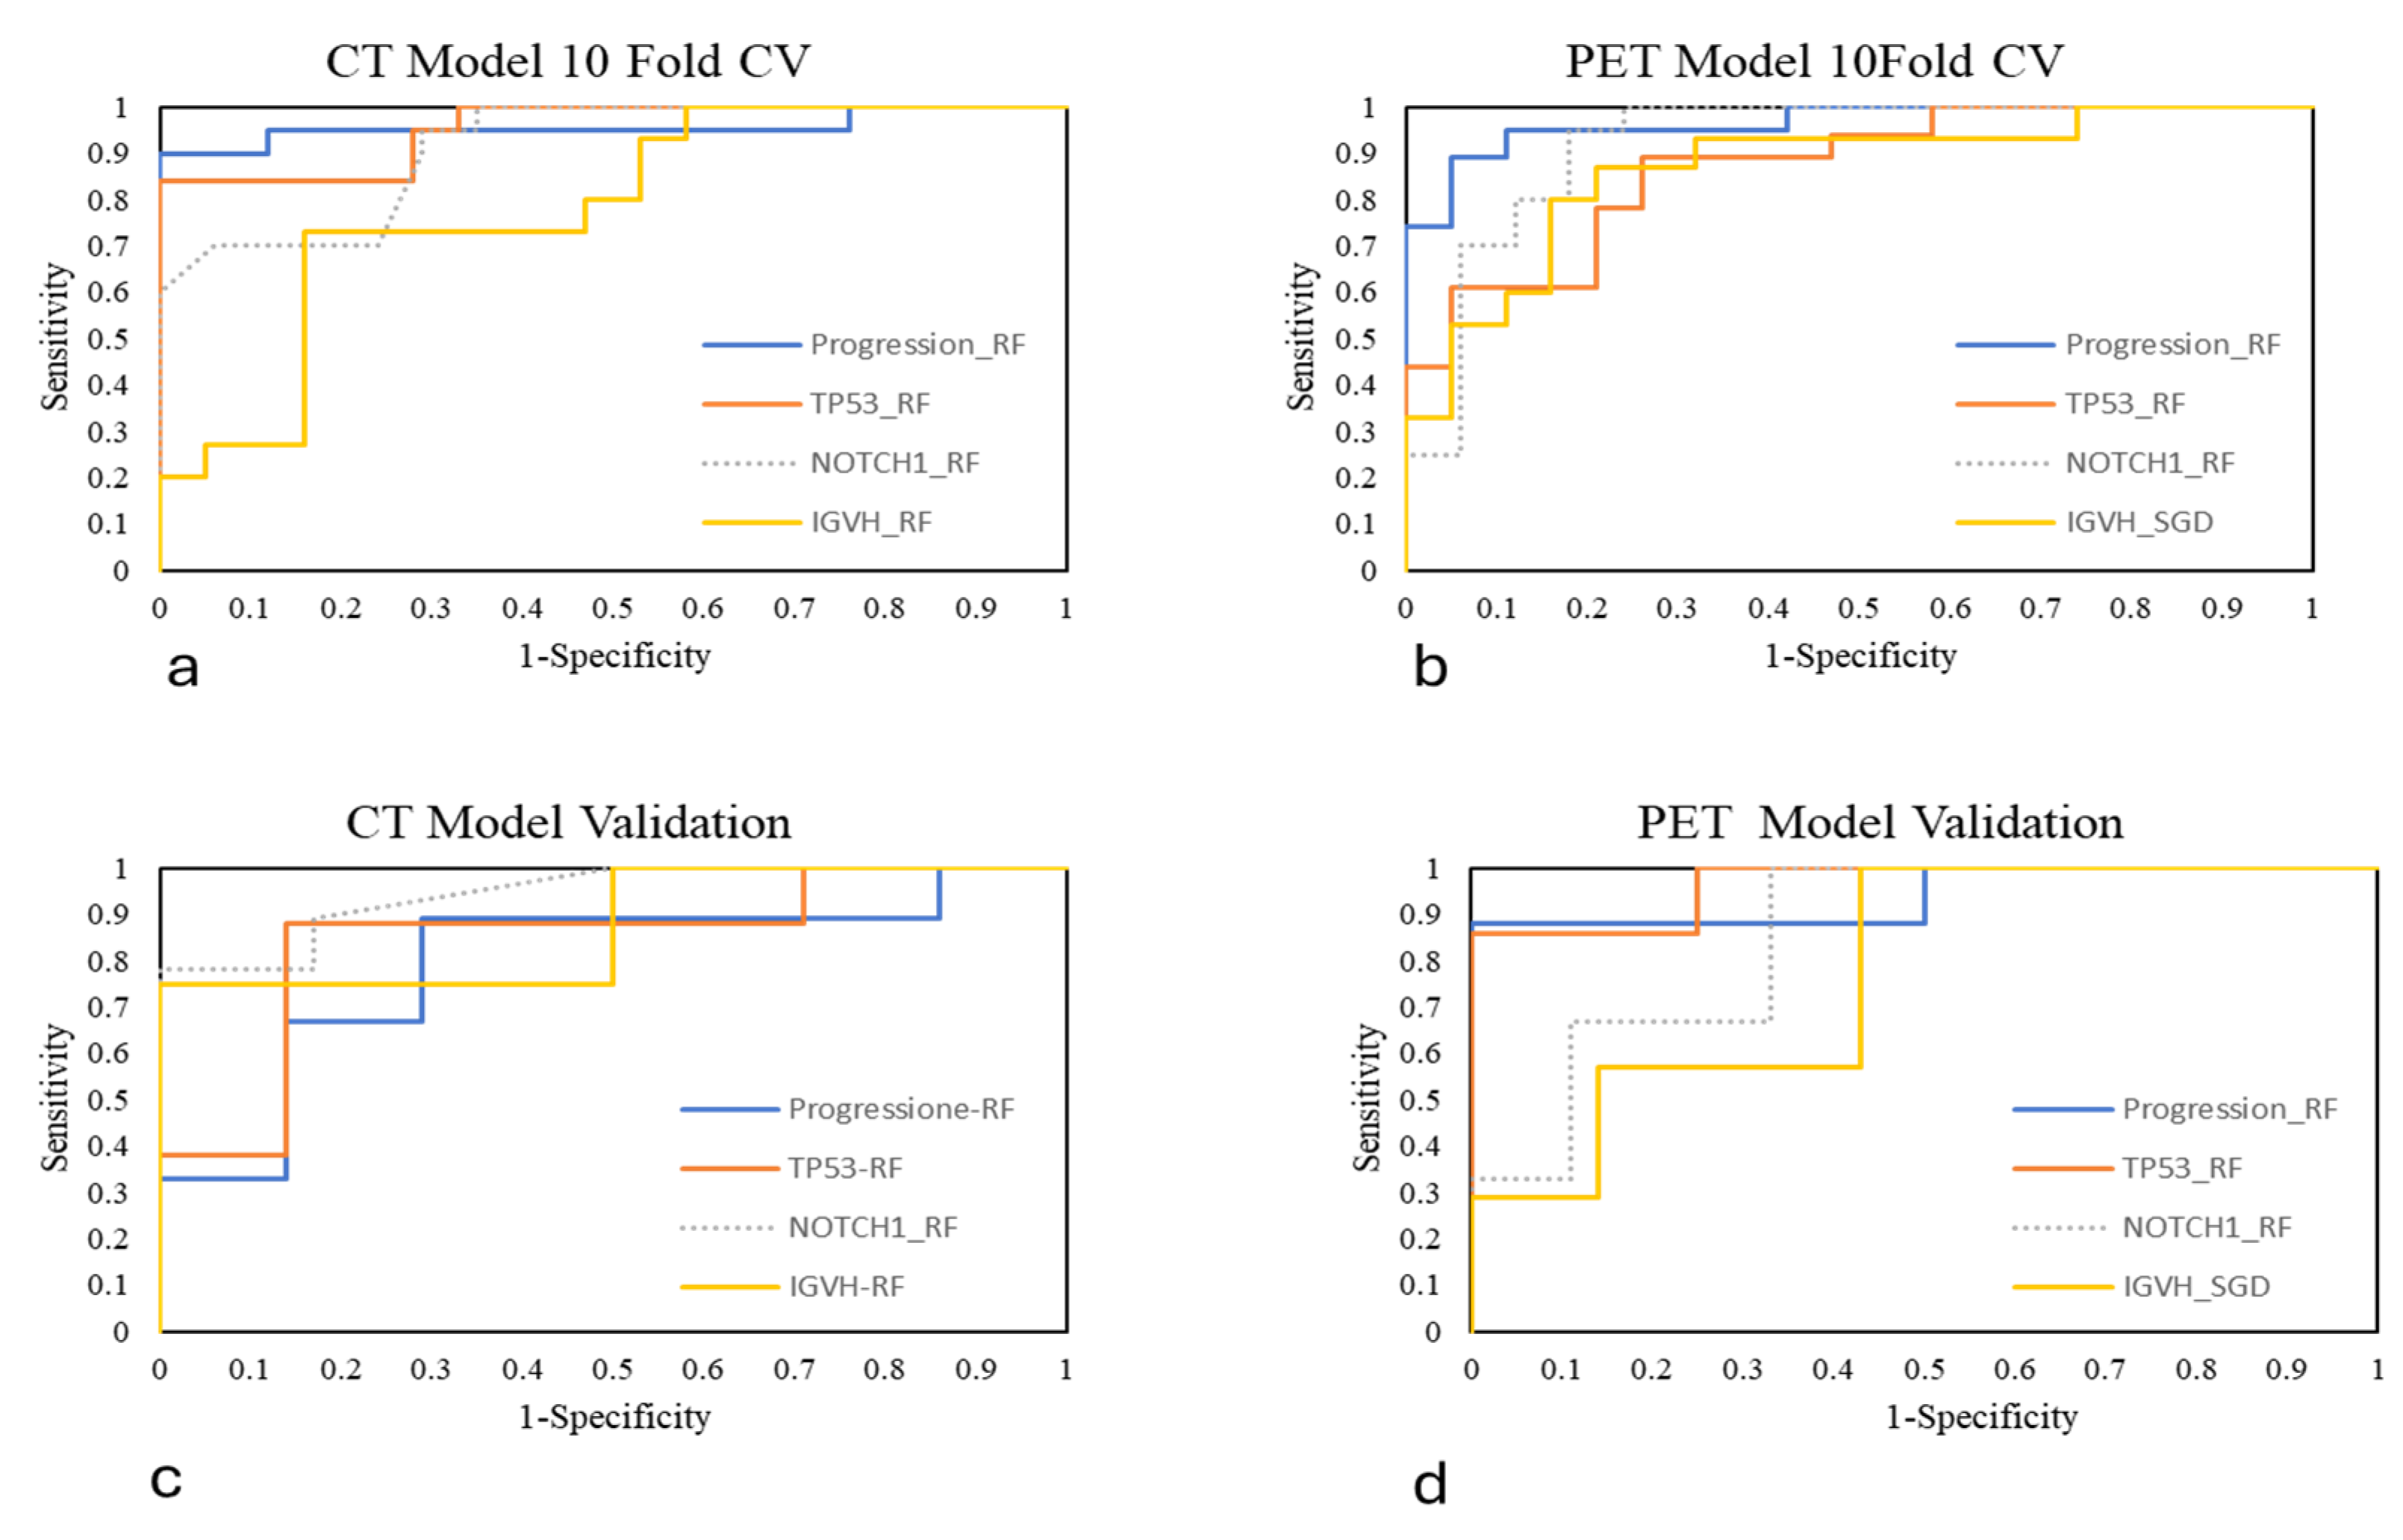

3.3. Machine Learning Models’ Performances

| CT_10-Fold CV | AUC | CA | Precision | Sensitivity | Specificity |

|---|---|---|---|---|---|

| Progression_RF | 0.96 | 0.92 | 0.92 | 0.92 | 0.93 |

| TP53_RF | 0.95 | 0.81 | 0.81 | 0.81 | 0.81 |

| NOTCH1_RF | 0.91 | 0.81 | 0.84 | 0.81 | 0.83 |

| IGVH_RF | 0.78 | 0.68 | 0.69 | 0.68 | 0.69 |

| PET_10-Fold CV | |||||

| Progression_RF | 0.96 | 0.90 | 0.90 | 0.90 | 0.90 |

| TP53_RF | 0.87 | 0.81 | 0.82 | 0.81 | 0.82 |

| NOTCH1_RF | 0.92 | 0.87 | 0.87 | 0.87 | 0.86 |

| IGVH_SGD | 0.84 | 0.77 | 0.79 | 0.77 | 0.79 |

| CT Model | AUC | CA | Precision | Sensitivity | Specificity | TP | TN |

|---|---|---|---|---|---|---|---|

| Progression_RF | 0.94 | 0.87 | 0.87 | 0.87 | 0.86 | 0.80 | 0.73 |

| TP53_RF | 0.94 | 0.87 | 0.90 | 0.87 | 0.91 | 0.87 | 0.86 |

| NOTCH1_RF | 0.94 | 0.87 | 0.90 | 0.87 | 0.91 | 0.80 | 0.8 |

| IGVH_RF | 0.94 | 0.87 | 0.90 | 0.87 | 0.91 | 0.43 | 0.86 |

| PET Model | |||||||

| Progression_RF | 0.88 | 0.75 | 0.75 | 0.75 | 0.75 | 0.87 | 87.50 |

| TP53_RF | 0.96 | 0.80 | 0.81 | 0.80 | 0.81 | 0.90 | 0.91 |

| NOTCH1_RF | 0.85 | 0.67 | 0.68 | 0.67 | 0.73 | 0.89 | 0.83 |

| IGVH_SGD | 0.87 | 0.71 | 0.76 | 0.71 | 0.75 | 0.67 | 0.60 |